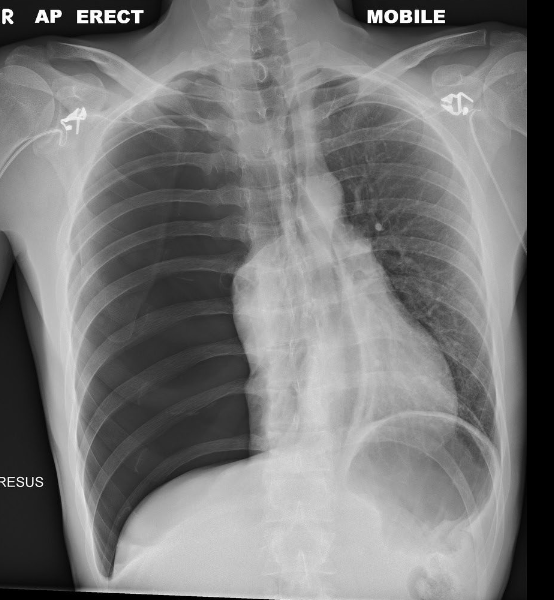

Pathology?

Pneumothorax